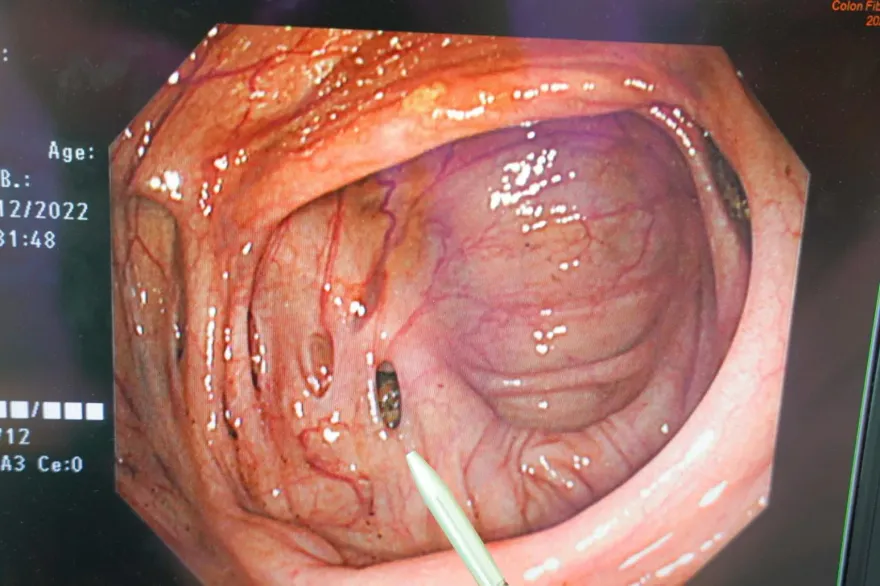

大腸鏡檢查

膀胱大腸相通

陳榮堅醫師

腹腔鏡手術

尿液感染

肛門滲漏

膀胱壁破裂